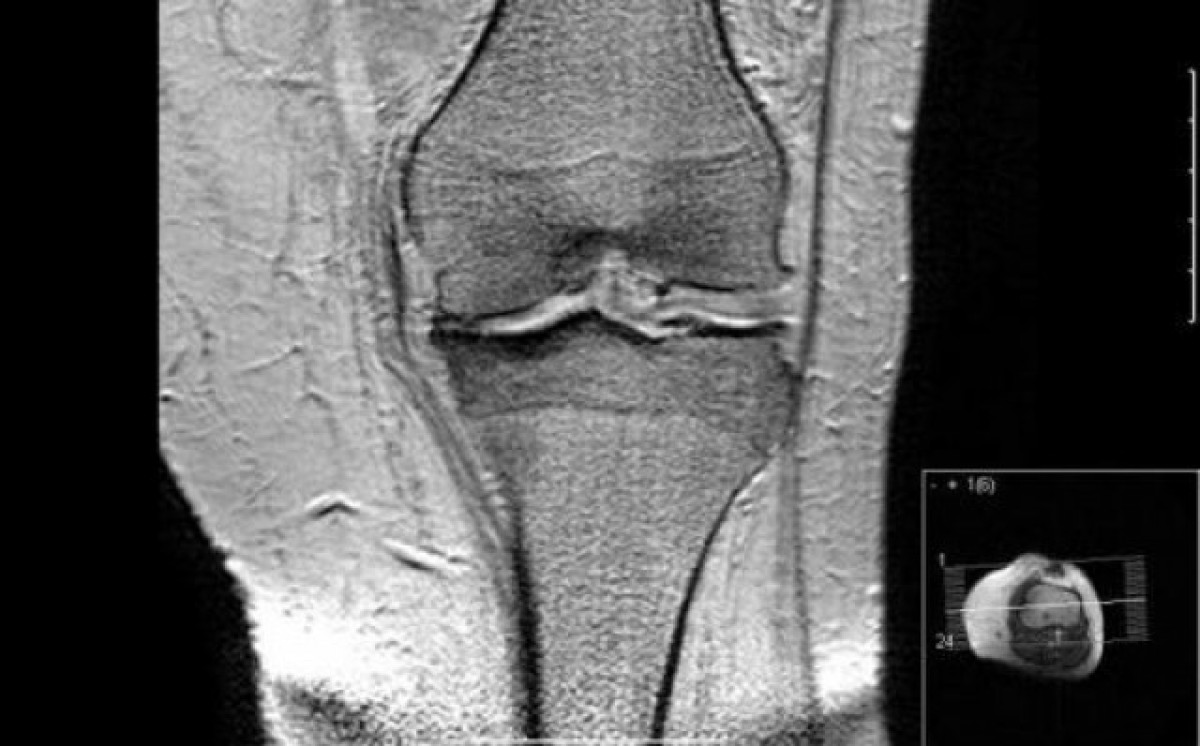

Les associacions, al contrari que Sanitat, han reivindicat que els sysadoa, "que costen al voltant d'uns 10 euros al mes", són eficaços i segurs. "Són eficaços en el tractament simptomàtic de l'artrosi i haurien de continuar sent finançats en les indicacions clíniques precises d'artrosi de genoll i mans i comorbiditats associades", han defensat.